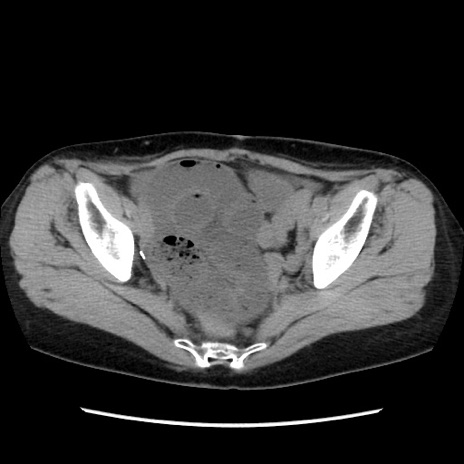

症例32(横断像)

【症例】40歳代 女性

【主訴】上腹部痛、嘔気・嘔吐

【現病歴】約9時間前頃から急に上腹部痛、嘔気、嘔吐が出現。改善しないため救急要請。

【既往歴】子宮頚癌(広汎子宮全摘術、放射線療法)、腸閉塞

【身体所見】腹部:平坦、軟、腸雑音亢進、上腹部を中心に腹部全体に圧痛あり。

【データ】WBC 8400、CRP 0.03